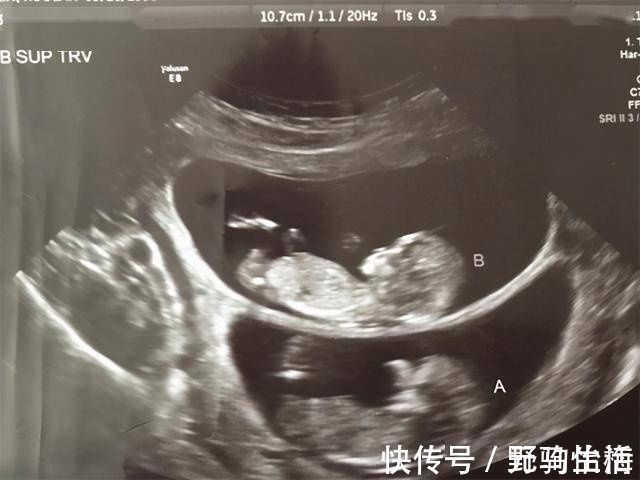

文章插图

相对于直接测量的结果, B超产检这种通过超声波的方式,隔着妈妈的肚皮、子宫和羊水的多重障碍来测量宝宝的发育情况,其中存在的误差就更多了。所以,在临床的检查上,B超只能算是一个接近实际的估算测量,并不等于宝宝的实际发育情况。

而且,B超对于胎儿发育情况的估算,主要参考的几个数值是: 双顶径、头围、腹围、股骨长、头臀径等 的各个肢体长度。然后再通过这些测量出来的数值来做发育情况的对比,从而间接的得出宝宝具体的发育情况,这就比较容易在对比之中存在着发育早晚的情况。